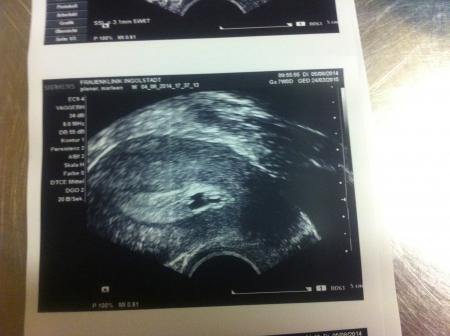

...das dritte und letzte für heute!

Naja, ob das jetzt ein Hämatom ist oder was auch immer, irgendwas wird es schon sein. Ich hoffe nur, dass mein kleiner Krümel nun endlich wächst und die OP auchngut überstanden hat! Ich danke euch allen; die an mich und meinem Krümel glauben und mir immer die Daumen drücken. laut Berechnungen auf dem US Gerät bin ich 5+3 oder 5+6 also 6.Ssw.

Nur mit dem erkennen tue ich mich schwer. kann eine von euch was gutes erkennen?

Also das sieht doch gut aus.Blut kann man nicht sehen... es wäre schwarz zu erkennen... und ich meine man kann viel sehen in der Fruchthöhle....den Dottersack und wenn ich mich nicht täusche auch das kleine würmchen in der ecke... Deine Geschichte ist wirklich unglaublich.... Ich drücke dir weiter die Daumen !!! Und denk ganz viel an dich und dein kleinen tapferen Krümel!